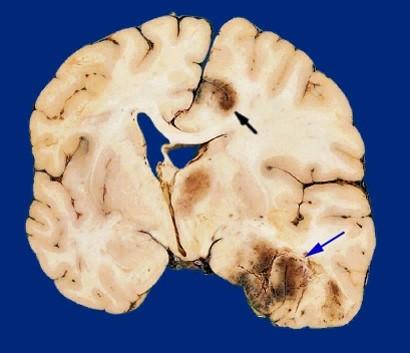

what was likely going on here

hemorrhage and edema

what is going on here

hydrocephalus